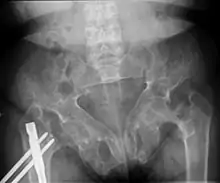

Brown tumors in the pelvis and a hip fracture.[13]